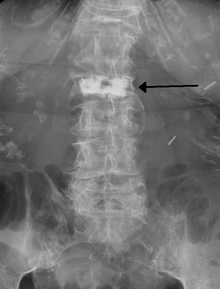

Cement in a vertebra as seen on plain Xray.

Kyphoplasty is a variation of a vertebroplasty which attempts to restore the height and angle of kyphosis of a fractured vertebra (of certain types), followed by its stabilization using injected bone cement. The procedure typically includes the use of a small balloon that is inflated in the vertebral body to create a void within the cancellous bone prior to cement delivery. Once the void is created, the procedure continues in a similar manner as a vertebroplasty, but the bone cement is typically delivered directly into the newly created void.